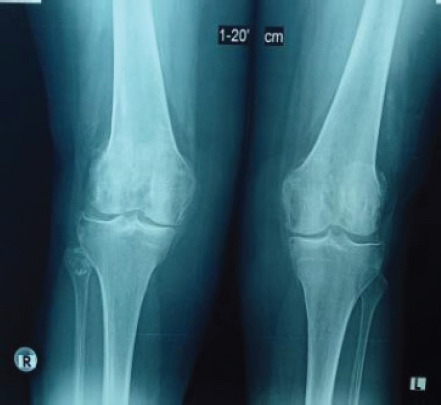

Case report: A 71-year-old Caucasian woman presented to our orthopedic department due to chronic right knee pain, which had worsened over the past year. She was diagnosed with osteoarthritis and was scheduled for a TKA. Three years postoperatively, she returned for examination due to anterior knee pain. Patellar instability was observed and intensive extensor mechanism strengthening and physiotherapy were recommended. Three months later, she presented with severe pain and inability to move her knee. Imaging revealed a fracture and dislocation of the patella. She was surgically treated with lateral release and proximal realignment of the extensor mechanism, according to Insall procedure, with great post-operative outcome.